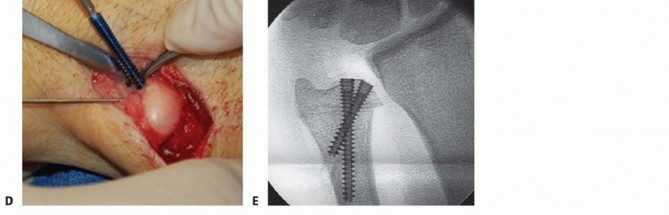

With the diaphysis exposed, we apply the dedicated cutting jig. The jig is temporarily fixed to the bone using bicortical screws. We utilize a sharp, cooled oscillating saw to execute the osteotomy. Copious cold saline irrigation is non-negotiable during the cutting phase to prevent thermal necrosis of the bone ends, which is a major contributor to nonunion. We make the proximal cut first, followed by the distal cut, removing the precisely templated wafer of bone. The oblique nature of the cut (usually 45 degrees) allows the bone ends to slide seamlessly together without rotational malalignment.

Following the resection, the compression device integrated into the jig is activated. We slowly and deliberately compress the osteotomy site until